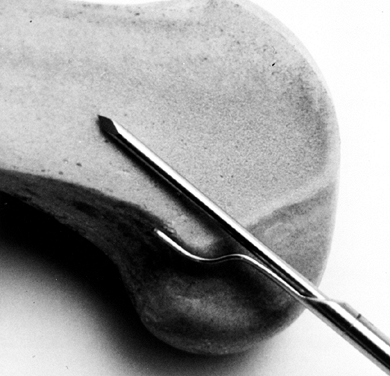

#5 Ticron suture in each hole (Fig. 89.7).

Figure 89.7.

Photograph of the harvested tendon. Place two #5 Ticron sutures in the

tibial bone plug and mark the distal cortical surface of the tibial

plug with the marking pen. Mark the tendo-osseous junction of the

femoral bone plug as well. Bone plugs are approximately 25 mm long,

with a tendon length of 42 mm. -